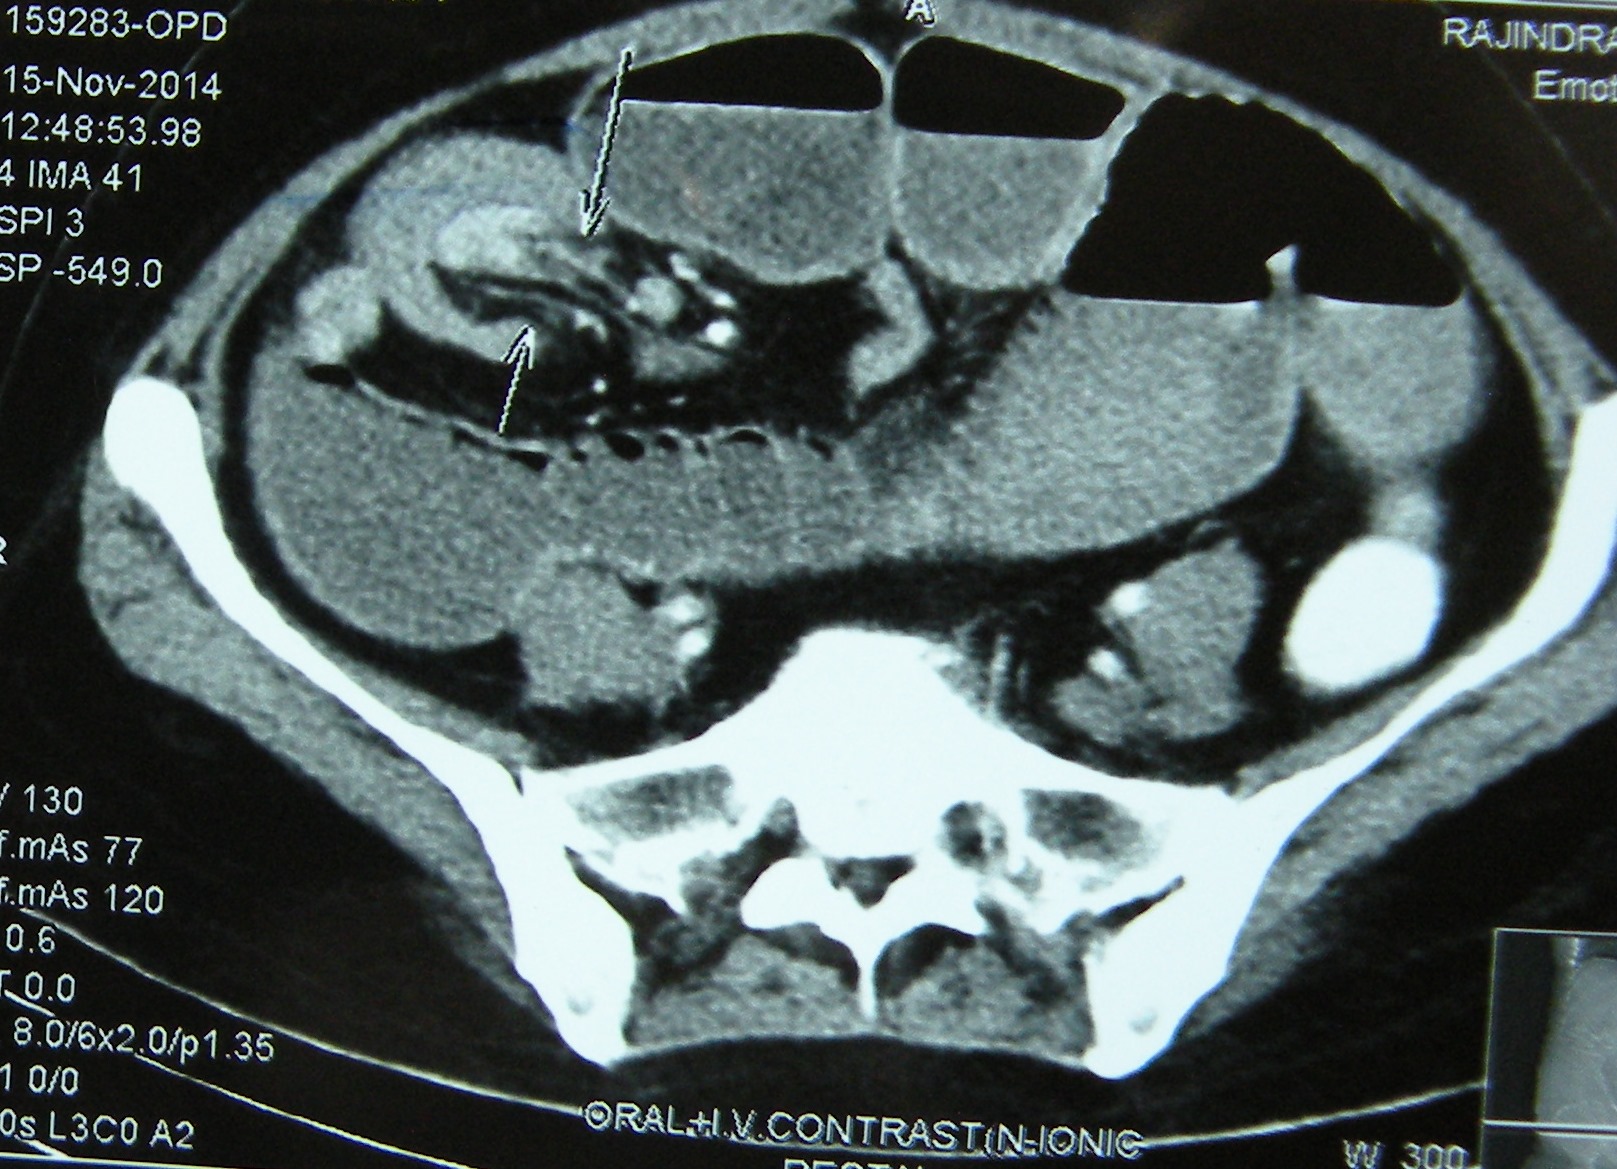

20.11.14 An adult intussusception, diagnosed on US and CT, in a 50-years old female, presenting with sub-acute intestinal obstruction of many weeks, was treated by resection of the segment of distal ileum bearing the intussusception. On cut section, it was found to contain a big pedunculated benign-looking tumour arising from the ileum.